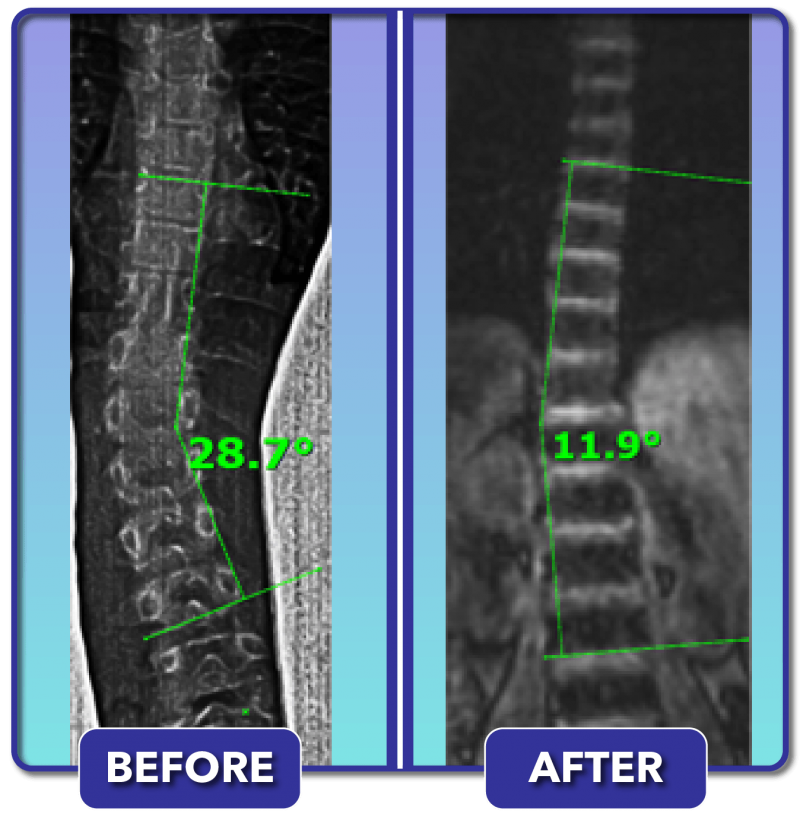

Scoliosis Before and After Treatment Results Scoliosis Care Centers

From scoliosiscarecenters.com

Scoliosis Before and After Treatment Results Scoliosis Care Centers Can You Run After Scoliosis Surgery Patients should expect to follow plenty of dos and don'ts in the months after surgery that can help smooth their recovery, according to praveen kadimcherla, md, an. In general, you can do regular sports 3 to 6 months after scoliosis surgery, but again it is important to follow your specialist’s recommendations. Yes, you can, although the more important question is. Can You Run After Scoliosis Surgery.